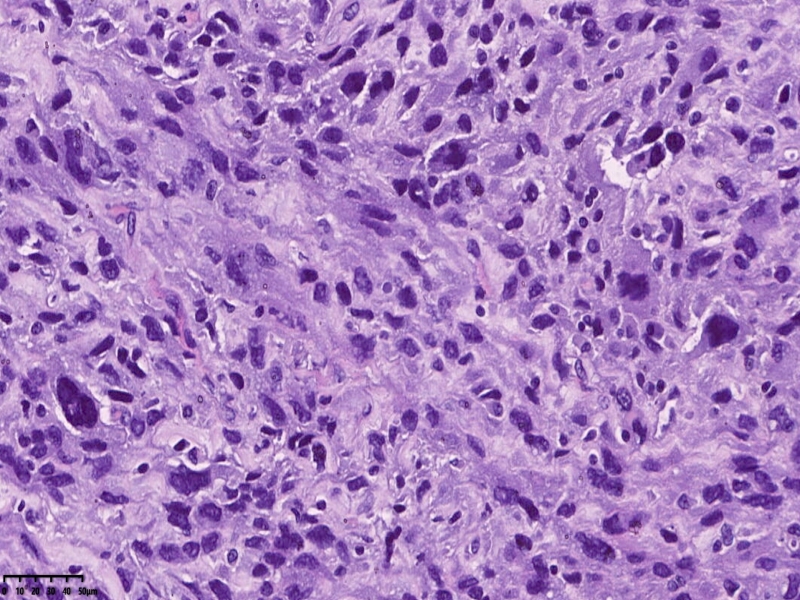

镜下可见肌间可见梭形瘤细胞,细胞核畸形,多核瘤巨细胞。坏死。

会诊结果:子宫体间叶组织来源的肿瘤,形态学符合恶性。依据免疫组化结果,可排除肌源性肿瘤、胃肠间质瘤、子宫内膜间质肿 瘤、神经源性肿瘤、孤立性纤维性肿瘤等。 考虑可能为纤维肉瘤。